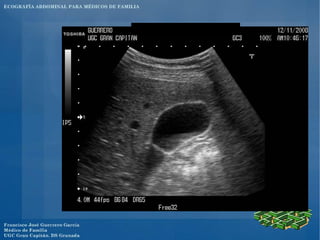

El documento presenta un programa de ecografía abdominal para médicos de familia que incluye presentaciones sobre generalidades de la ecografía y anatomía normal de los órganos abdominales los jueves, y sobre imágenes anormales en ecografía abdominal y ecografía obstétrica los viernes, con un caso clínico el sábado en el centro.